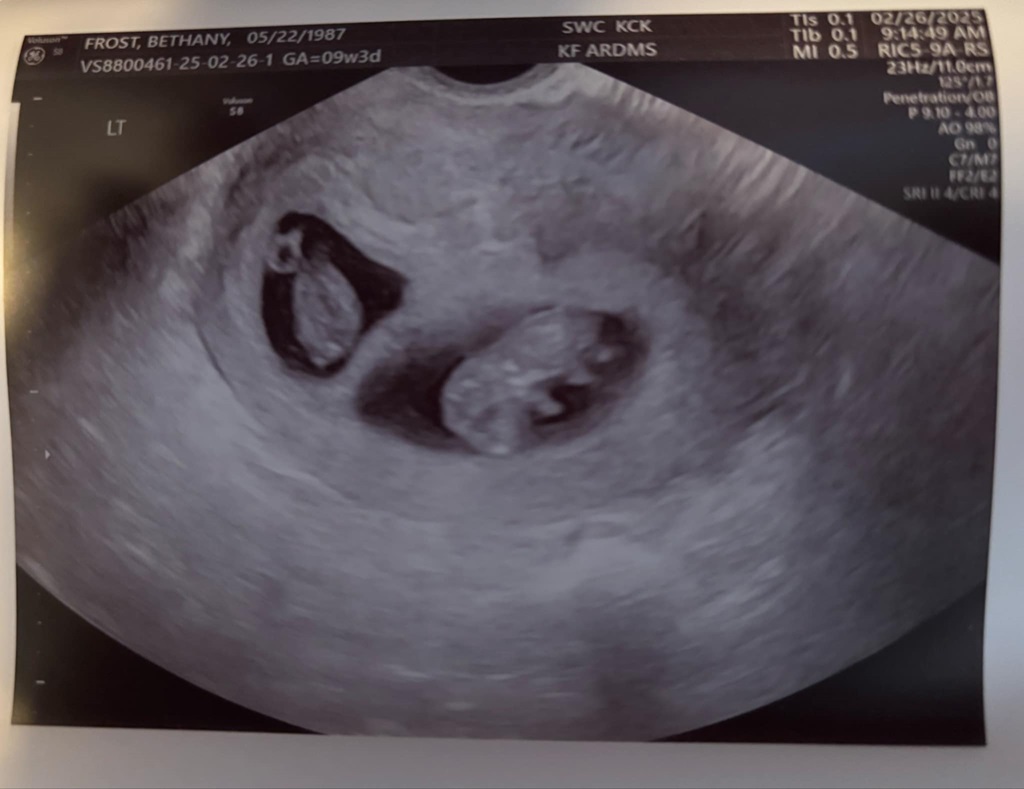

That’s right… twins. Not only did I defy the odds of getting pregnant at all, especially for my age. But I’m having twins. They’re called Di/Di twins. 2 separate eggs, so they each have their own little apartment separate from each other. Apparently this is great because there’s less risk for them to wrap cords around each other and so on. It also means we can end up with: boy/girl, boy/boy, girl/girl. Both are also an interesting anomaly according to the sono tech. Twins usually measure about a week off from each other. So one will measure 9 weeks, and the other 8 weeks. NOPE! Both are measuring 9 weeks 3 days. They both also currently have the same exact heartbeat of 171!! It was so cool to hear it too. Since it is Twins, I am 100% high risk now. We are doing a genetics test in a couple weeks, then another sono with the high risk doctor.

So yea! What a year! Meet the Frost Twins!!!